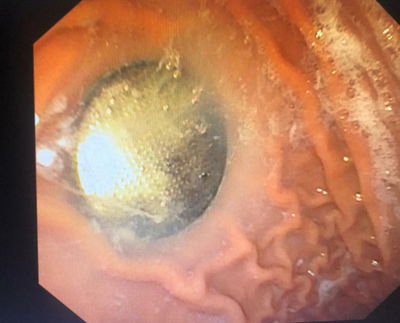

בתוך משמרת אחת בהדסה הר הצופים, שלושה מקרי בליעת חפצים מסכני חיים על ידי ילדים קטנים.

הפיסטוק, המטבע והסוללה – אותרו מיידית ונשלפו החוצה בהצלחה (בריאות)